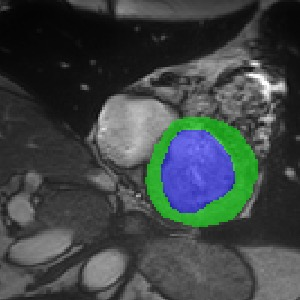

Transformers, the default model of choices in natural language processing, have drawn scant attention from the medical imaging community. Given the ability to exploit long-term dependencies, transformers are promising to help atypical convolutional neural networks (convnets) to overcome its inherent shortcomings of spatial inductive bias. However, most of recently proposed transformer-based segmentation approaches simply treated transformers as assisted modules to help encode global context into convolutional representations without investigating how to optimally combine self-attention (i.e., the core of transformers) with convolution. To address this issue, in this paper, we introduce nnFormer (i.e., Not-aNother transFormer), a powerful segmentation model with an interleaved architecture based on empirical combination of self-attention and convolution. In practice, nnFormer learns volumetric representations from 3D local volumes. Compared to the naive voxel-level self-attention implementation, such volume-based operations help to reduce the computational complexity by approximate 98% and 99.5% on Synapse and ACDC datasets, respectively. In comparison to prior-art network configurations, nnFormer achieves tremendous improvements over previous transformer-based methods on two commonly used datasets Synapse and ACDC. For instance, nnFormer outperforms Swin-UNet by over 7 percents on Synapse. Even when compared to nnUNet, currently the best performing fully-convolutional medical segmentation network, nnFormer still provides slightly better performance on Synapse and ACDC.